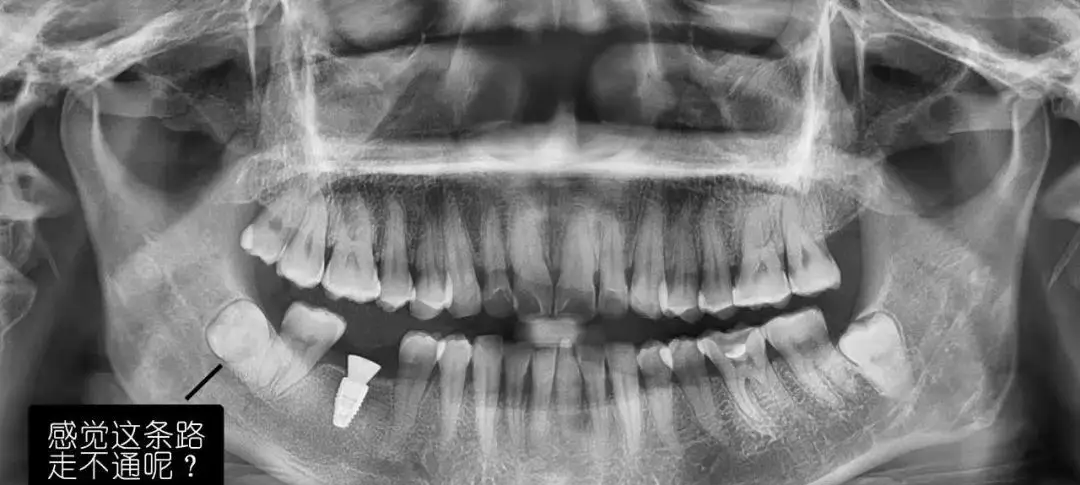

(7)种植牙。CBCT设备可以辅助种植手术的设计,制作种植导板,精确控制种植体的位置、方向、长度、直径等,最大程度利用患者现存骨量,优化种植体的位置,避免在种植手术过程中不慎破坏神经、鼻窦等解剖结构而导致颜面神经麻痹、鼻窦炎等并发症。使种植手术更安全便捷,确保手术及后期修复的成功。